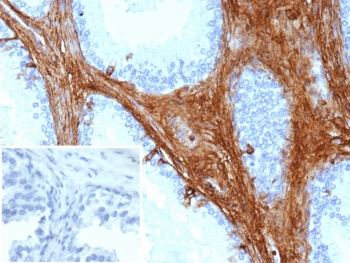

Decorin Antibody Prostate Carcinoma Immunohistochemistry. IHC staining of FFPE human prostate carcinoma tissue with microarray validated Decorin antibody (clone DCN/3521). Inset: PBS used in place of primary Ab (secondary Ab negative control). HIER: boil tissue sections in pH 9 10mM Tris with 1mM EDTA for 20 min and allow to cool before testing.